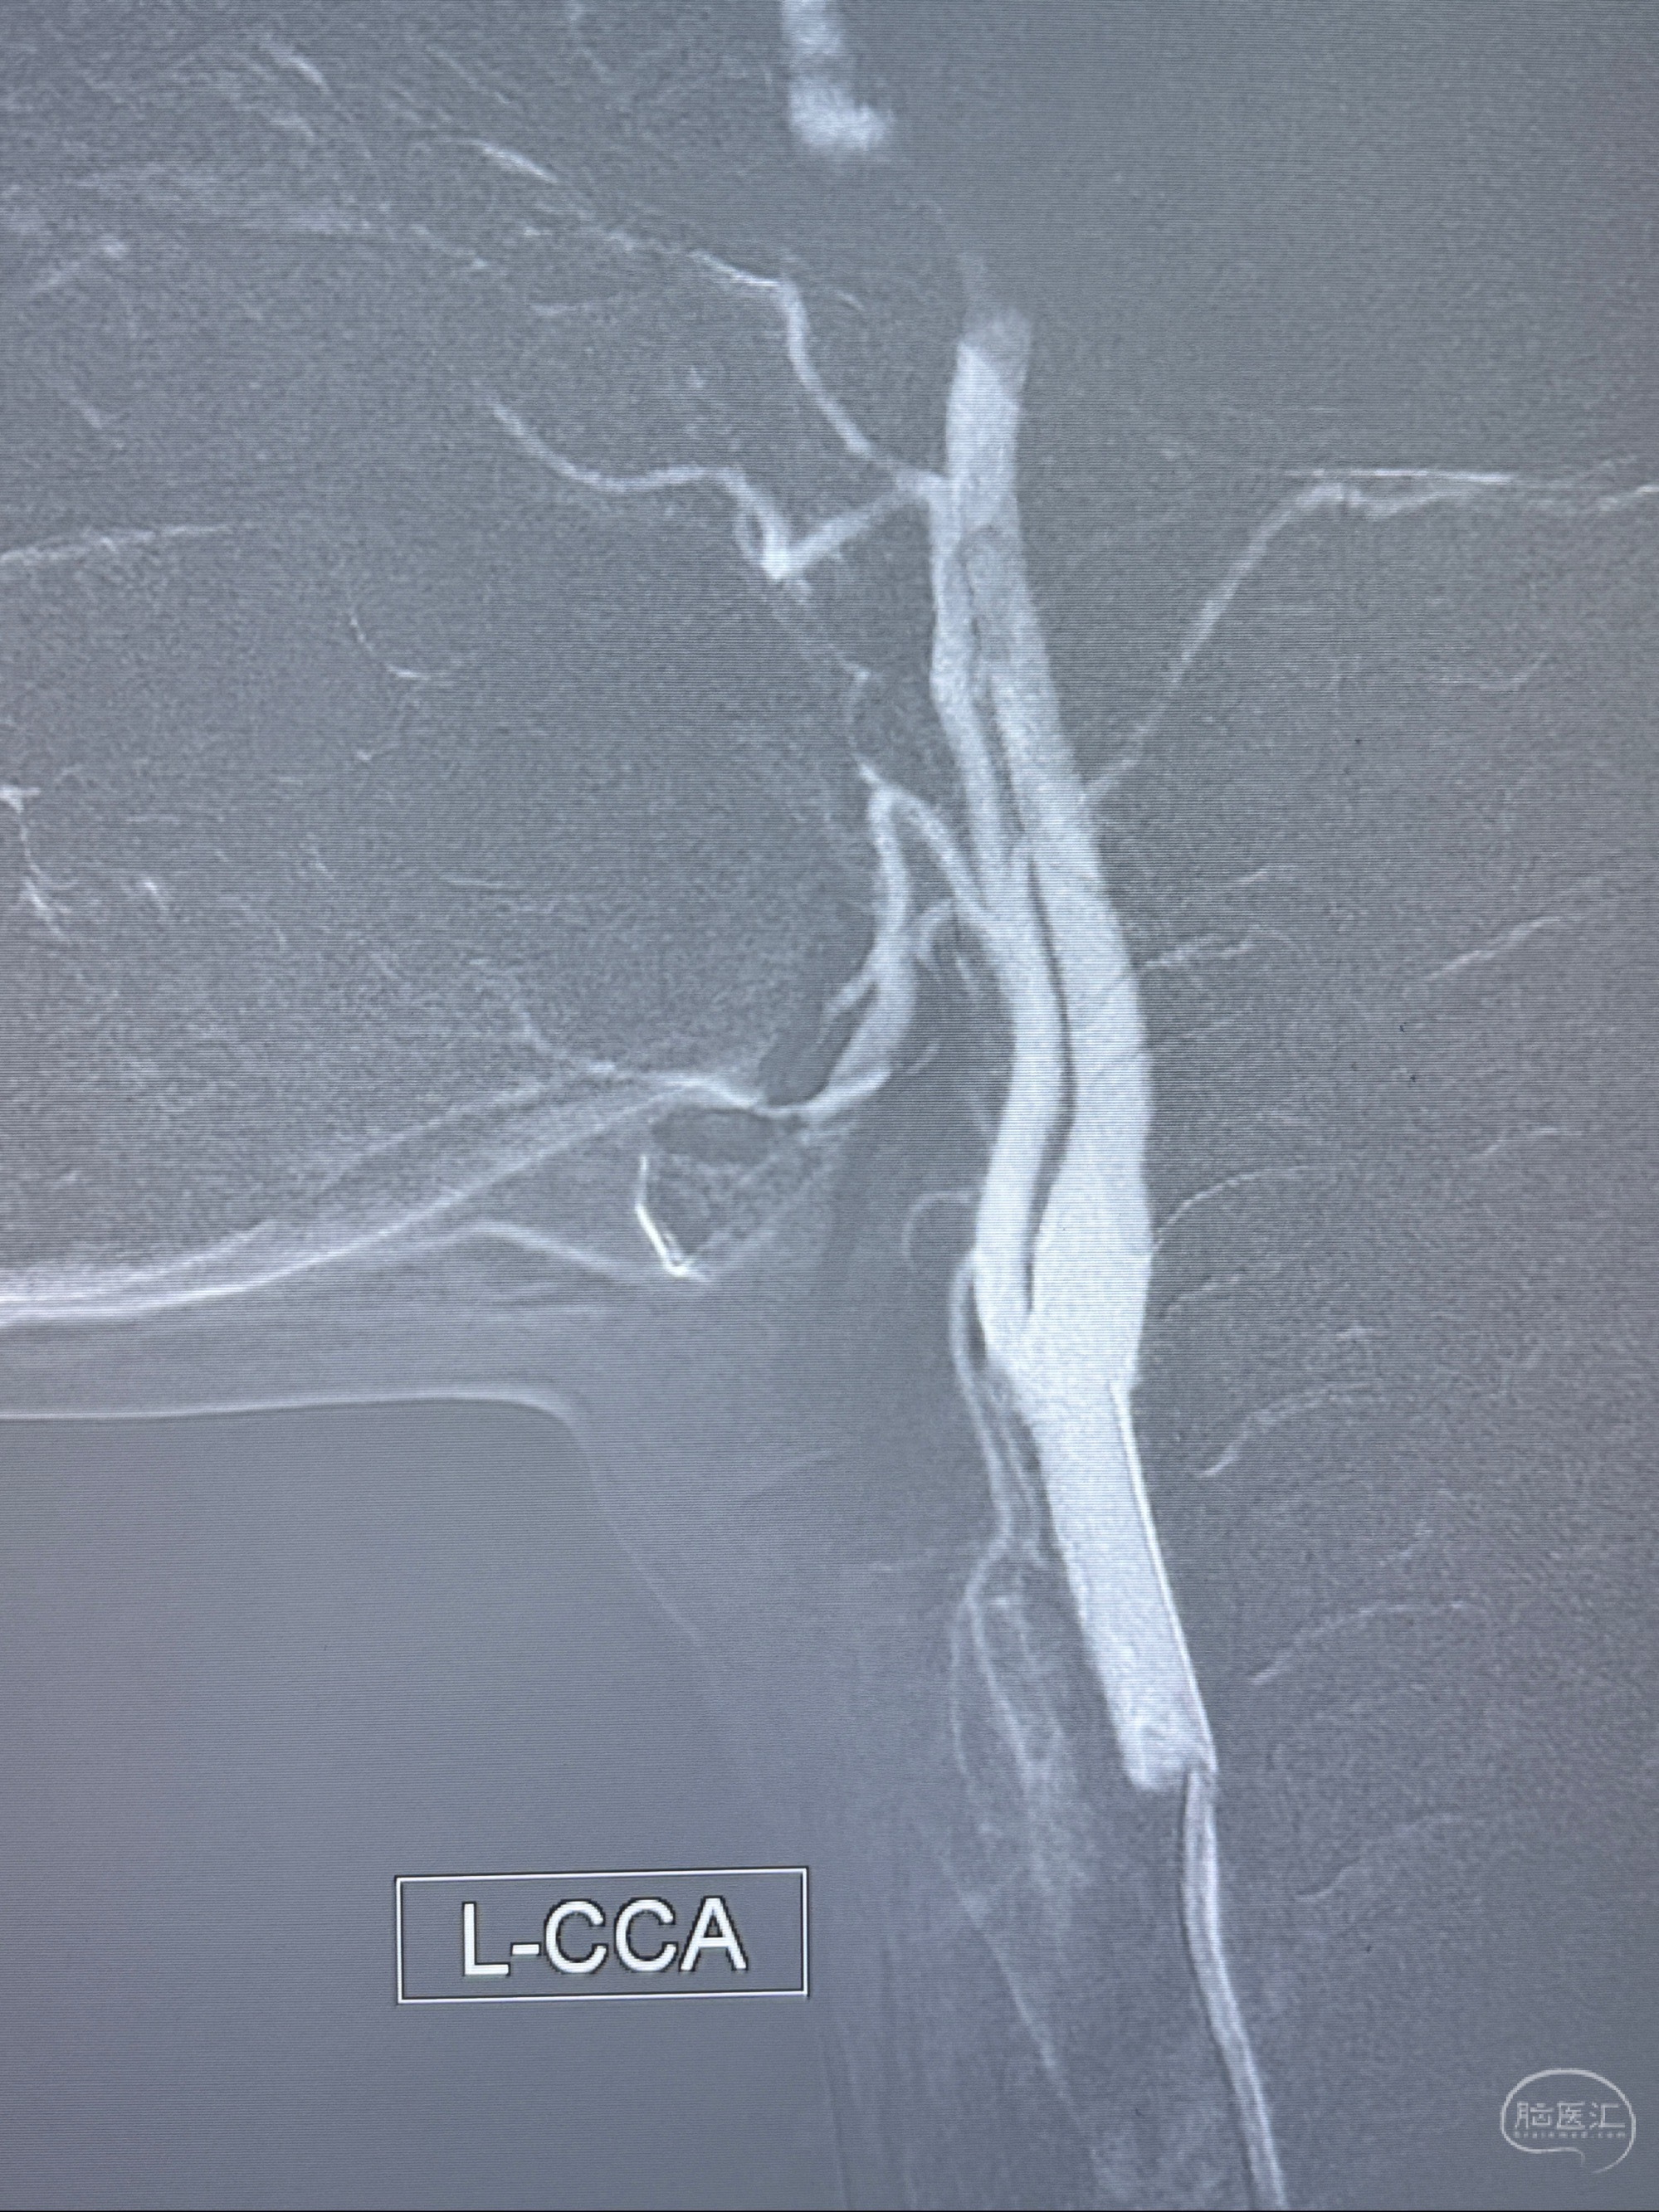

2023-11-03 蓝十字脑科医院 头颅CTA:左侧颈内动脉C6段微小动脉瘤可能(约2mm),右侧大脑前动脉A1段纤细(对侧优势),左侧大脑中动脉提前分叉。

1.左侧颈内动脉瘤

- 支架辅助治疗?